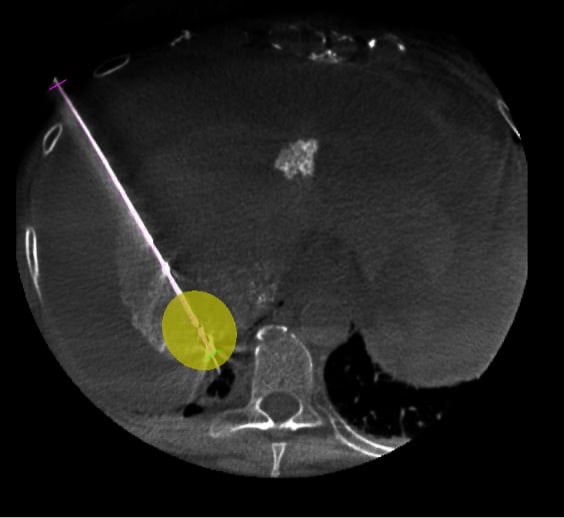

Equipped with sophisticated advanced image-guidance systems and multi-imaging modalities, our physicians may now better visualize and treat patients with complicated diseases. This system includes technology to make this easier in both 2D and 3D with dose reduction technology. It is equipped with integrated Intravascular Ultrasound. Vessel Navigation guidance, 2D Vessel Perfusion, 3D roadmap and Vessel quantitative measurements are offered as well. Vessel Navigator allows reuse of 3D vascular anatomical information from existing CTA and MRA datasets as a 3D roadmap overlay on live X-ray images. With its sophisticated visualization, it provides an intuitive and continuous 3D roadmap to guide you through vasculature during the entire procedure. The system is connected to our PACS system allowing us to visualize previous diagnostic images inside the room.

As the clinician moves the system, the image beam automatically maintains alignment with the patient, allowing more consistent visualization and enabling them to keep their focus on the treatment. In addition, the room has ability to perform cone-beam XperCT, which will allow us to move some interventional procedures from one of the CT scanners on the first floor of University, further freeing-up capacity for diagnostic CT.